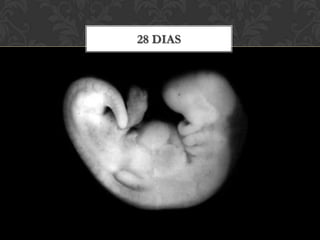

28 dias